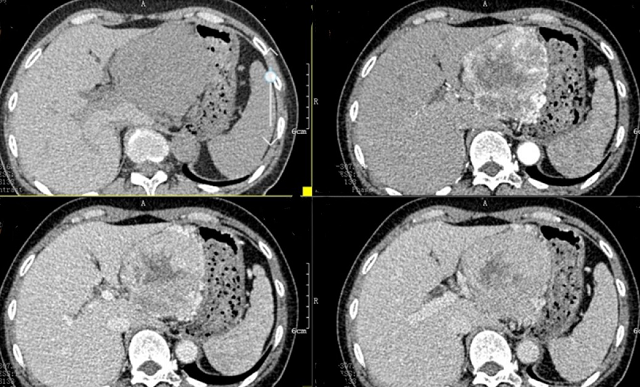

上腹部CT顯示胰腺巨大腫瘤

“CT表現(xiàn)符合胰腺神經內分泌腫瘤,穿刺也證實無誤,但是瘤體實在太大,直徑約12cm左右,腹腔內的門靜脈、腸系膜上靜脈、脾靜脈以及腹腔干這些重要血管統(tǒng)統(tǒng)包繞進去了,且與周圍結腸系膜也有累及!